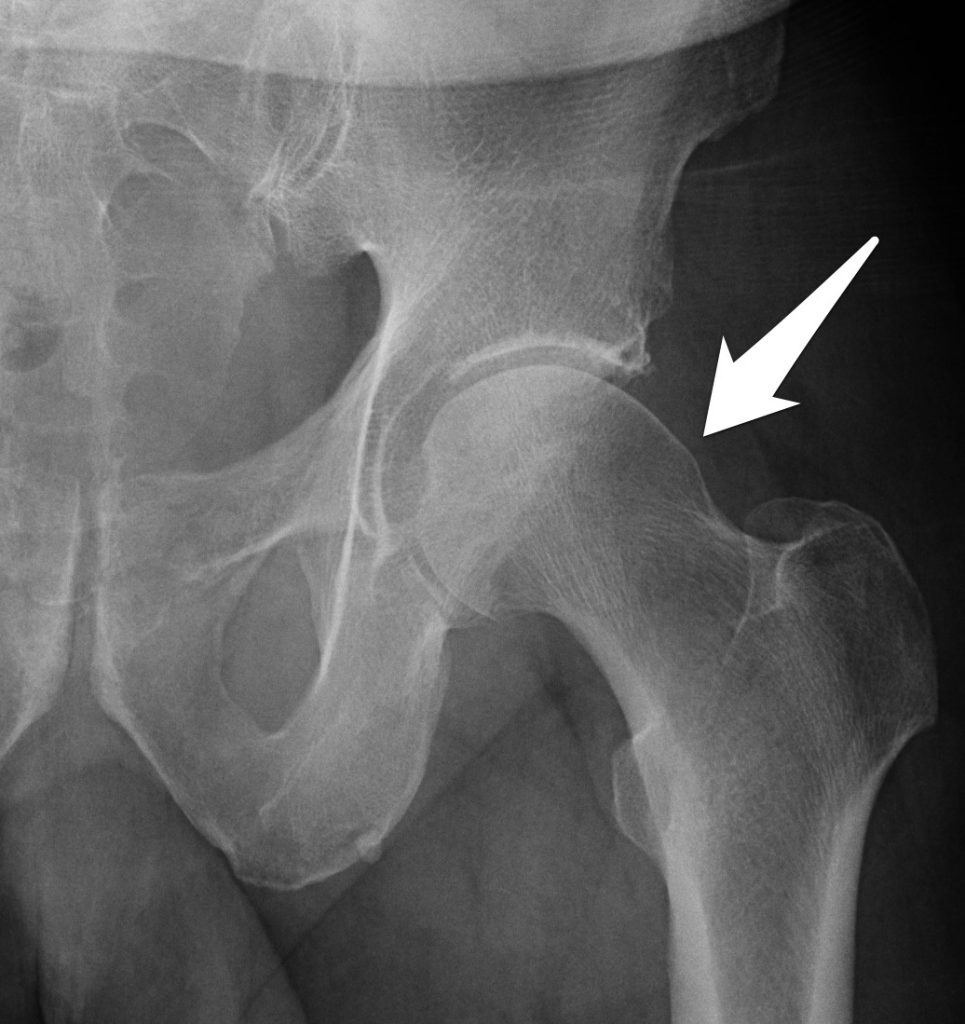

Signs of bilateral femuroacetabular CAM impingement (arrows). Figura Cam Type Impingement Syndrome This type results from a bony growth at the head of the femur. There are three types of fai: Cam lesion, in which the head of the femur is not shaped properly. Occurs if femoral head/neck bone is too. there are three types of fai: Refers to femoral based disorder usually in young athletic males. In some cases, physical. Cam Type Impingement Syndrome.